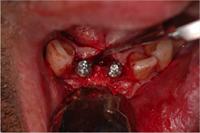

4. Implants placed

5. Area is overlaid with

Apatos

6. Four months later, the

is persistent in the area